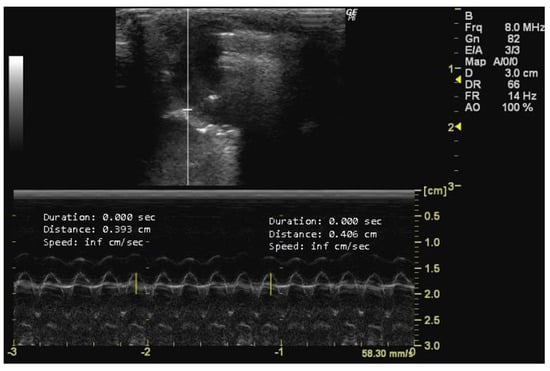

- How to measure HR